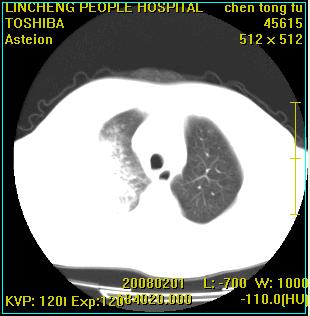

患者,男性,62岁。主因头晕,发热,咳嗽6天,高热达39度,esr19mm/h,wbc 3.9×10 9/l

大叶性肺炎并胸膜炎

实变区见空气支气管征,支气管通畅,考虑为大叶性肺炎,右侧少量胸水

1)考虑为:右肺感染性病变。建议:抗炎治疗复查。2)右侧少量胸腔积液。

考虑为右肺大叶性肺炎伴少量胸腔积液,建议复查,如病变不吸收或吸收不明显,建议纤维支气管镜检查,除外细支气管肺泡癌的可能。

请教各位,大叶性肺炎可以每个叶都有吗?不是多数发生在一个叶吗?跨叶的多吗?

考虑感染性病变,不除外细支气管肺泡癌建议:1、治疗后复查。2、作支纤镜检查。

实变区见空气支气管征,支气管通畅,考虑为大叶性肺炎,右侧少量胸水。